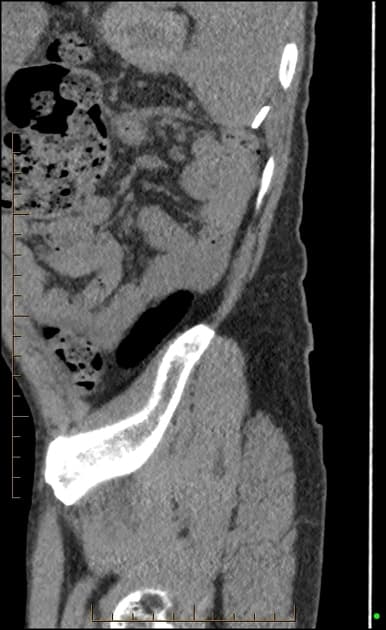

Sagittal C+ portal venous phase

- Hình ảnh CT cho thấy các quai ruột non giãn và các mức khí-dịch, phù hợp với tắc ruột non (small bowel obstruction).

- Vị trí chuyển tiếp tại hồi tràng cuối (terminal ileum) do dày thành vòng quanh và manh tràng có vẻ teo nhỏ.

- Một số hạch bạch huyết mạc treo (mesenteric lymph nodes) phì đại được thấy ở hố chậu phải.

- Vùng hồi manh tràng là vị trí thường gặp nhất của lao trong đường tiêu hóa. Tuy nhiên, hình ảnh học không đặc hiệu cho lao. Chẩn đoán phân biệt bao gồm bệnh Crohn và ung thư manh tràng (carcinoma of the cecum). Chẩn đoán lao đã được xác nhận bằng giải phẫu bệnh (histopathology).

Lao hồi manh tràng là vị trí phổ biến nhất của lao đường tiêu hóa, đặc biệt thường gặp ở vùng lưu hành và người suy giảm miễn dịch. Nhiễm trùng mạn tính do Mycobacterium tuberculosis gây viêm xuyên thành, dẫn đến dày thành ruột, hẹp lòng và biến đổi xơ. Hồi tràng cuối và manh tràng dễ bị tổn thương do chứa nhiều mô lympho và tình trạng ứ trệ nhu mô ruột. Các dấu hiệu hình ảnh điển hình gồm dày thành không đối xứng hoặc đối xứng, manh tràng teo nhỏ và hạch mạc treo phì đại hoại tử. Mặc dù hình ảnh gợi ý, nhưng không đặc hiệu và dễ nhầm với bệnh Crohn hay ung thư manh tràng. Do đó, cần bằng chứng vi sinh hoặc giải phẫu bệnh như u hạt hoại tử bã đậu hoặc trực khuẩn kháng cồn-xiêm dương tính để chẩn đoán xác định. Nhận biết sớm và điều trị kịp thời giúp ngăn ngừa biến chứng như thủng, rò và hẹp ruột.